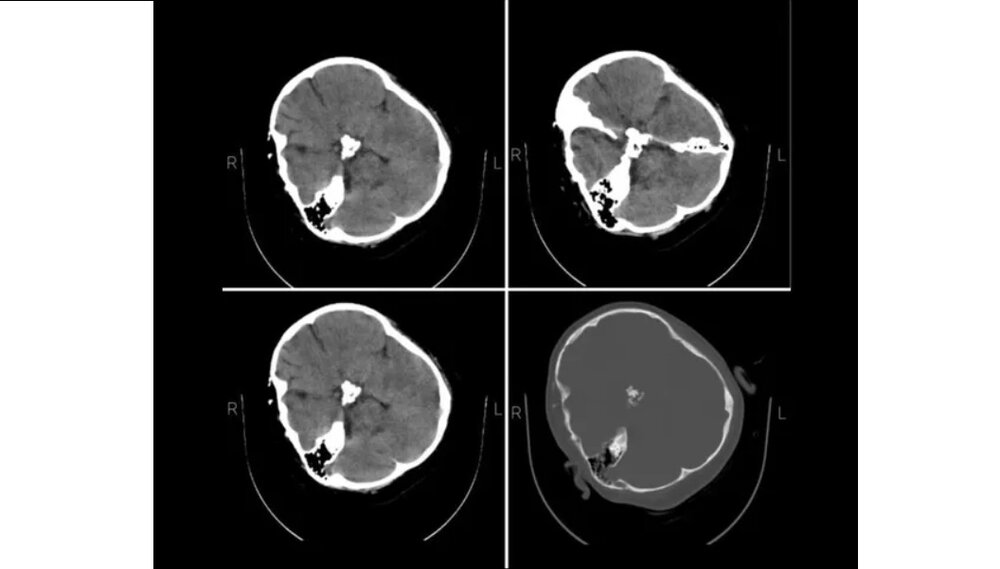

به گزارش هوشمند نیوز، در بیانیه متخصصین نرورادیولژی هیأت بورد رادیولوژی وزارت بهداشت که در پاسخ به استعلام ریاست نظام پزشکی صادر شده، آمده است: «با توجه به استعلام ریاست نظام پزشکی، متخصصین نرورادیولژی هیات بورد رادیولوژی وزارت بهدشت، پس از بررسی تصاویر سیتی اسکن مغز مرحومه مهسا امینی اعلام میدارد در سیتی اسکن که بهصورت فیلمبرداری از، مانیتور تهیه شده است، خونریزی در پارانشیم مغزی، خونریزی اپیدورال و سابدورال دیده نمیشود.»

گفتنی است که یکی از شبکههای خارجی پیشتر عکسی از سیتی اسکن مرحوم مهسا امینی منتشر کرده و مدعی شده بود که سیتی اسکن خانم مهسا امینی نشانگر شکستگی جمجمه، خونریزی و ادم مغزی است.